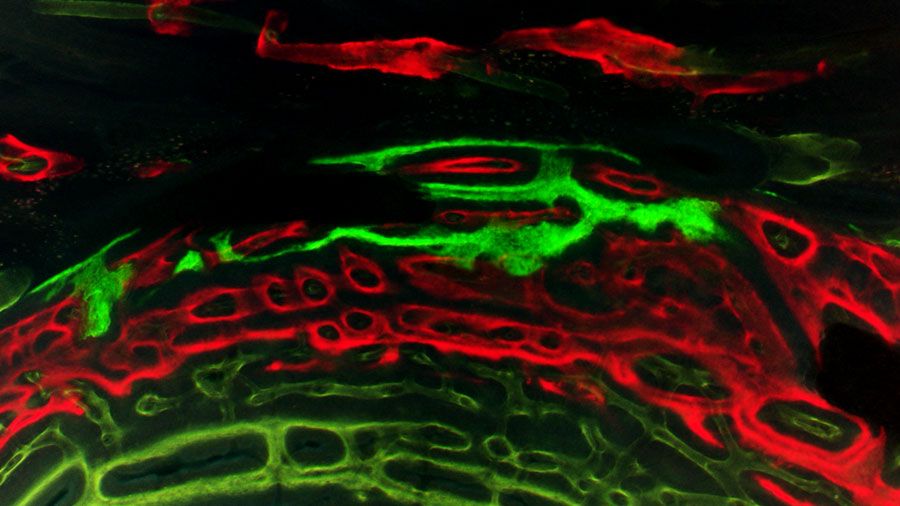

False colored scanning electron micrograph of a biofilm formed by Staphylococcus aureus on implant surface, showing fibrin formation in red